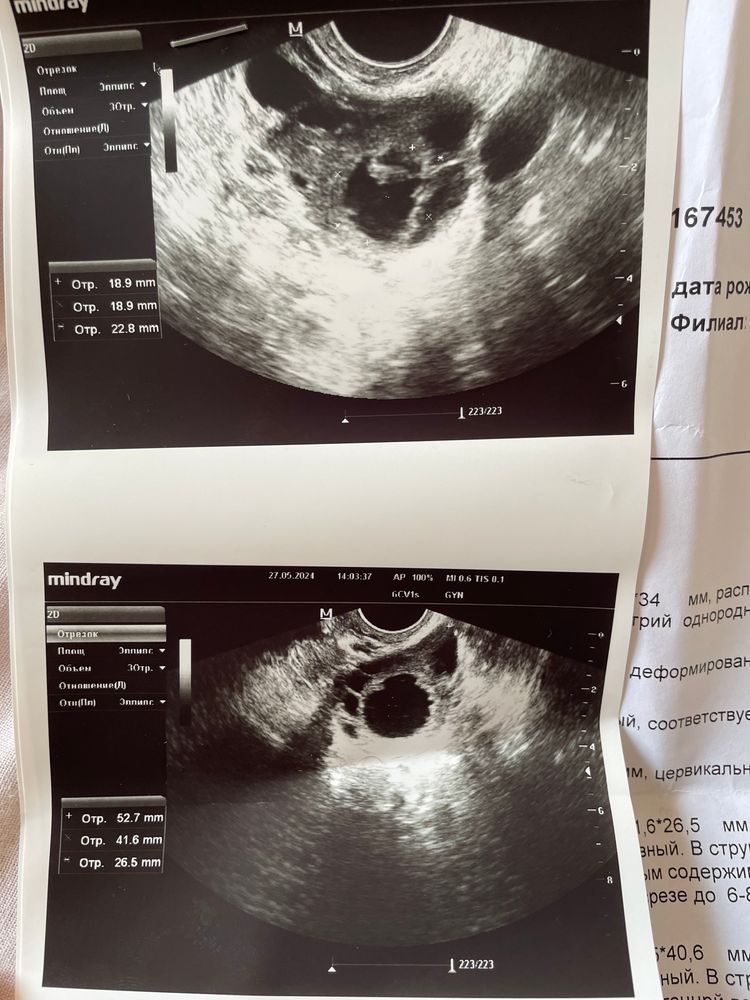

Была стимуляция овуляции клостом, выросло два фолликула, один 19мм другой 20 мм(в этот же день сделали укол хгч 10000). Спустя 4 дня после укола, сегодня пошла на узи подтвердить овуляцию, сказали один фолликул справа лопнул и есть немного жидкости в позадиматочном пространстве, а слева киста с кровоизлиянием. Похоже ли реально на кисту? Просто была не у своего репродуктолога, а у обычного гинеколога.